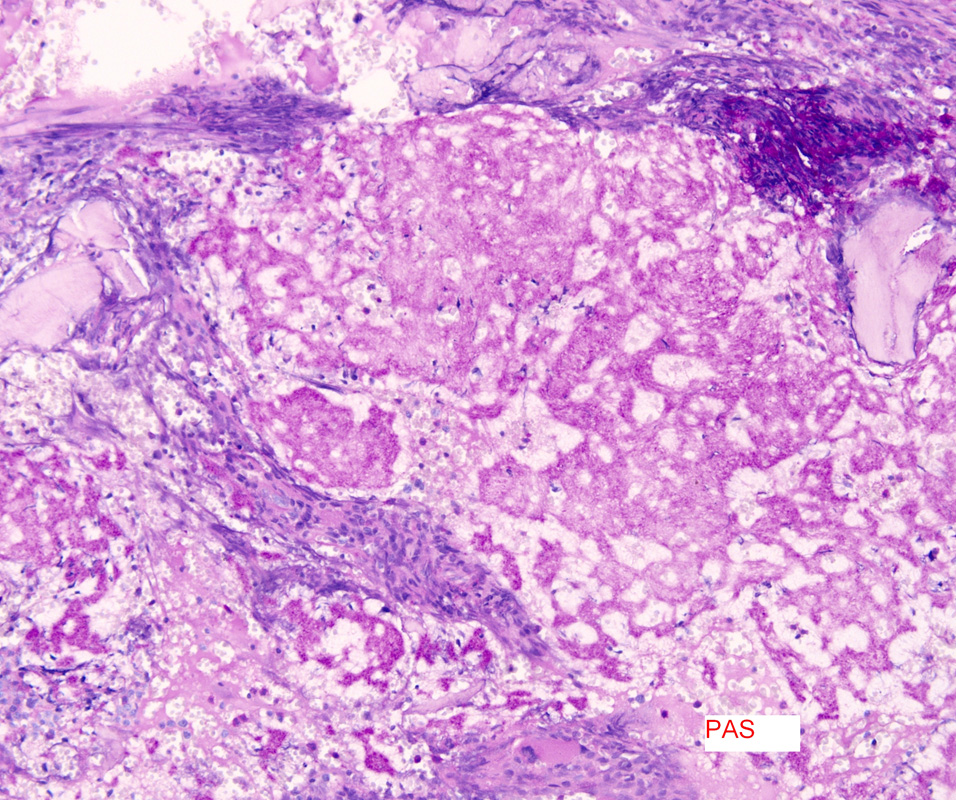

Case history: 17-year-old female with large, solid adnexal mass.

What is the diagnosis?

- Germ cell ...